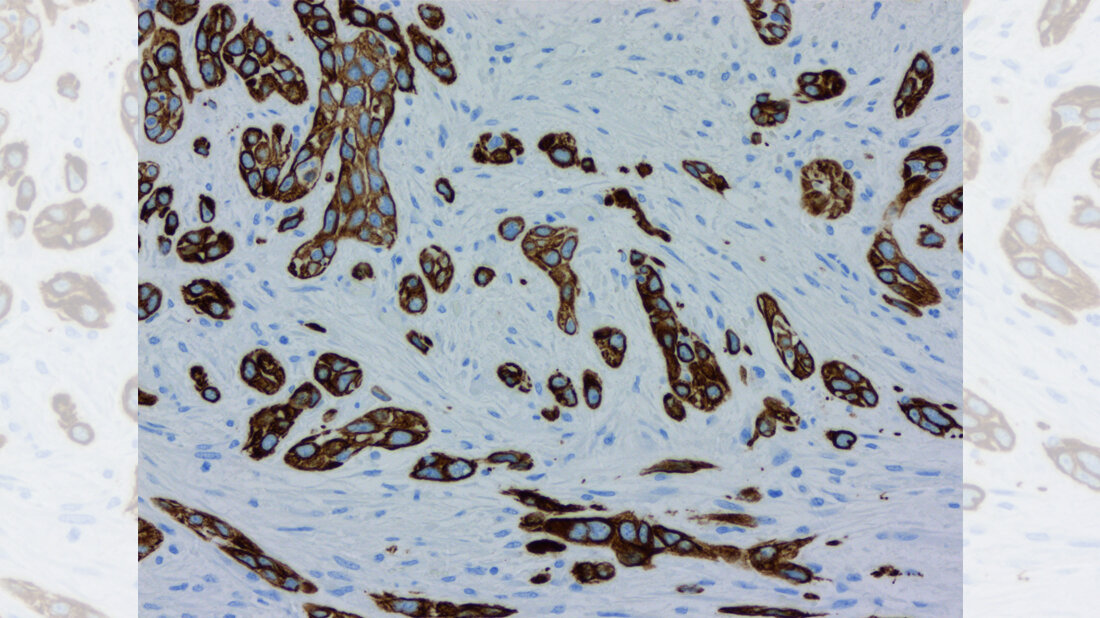

Laut Krebsinformationsdienst erkranken jedes Jahr etwa 19.000 Menschen in Deutschland an Bauchspeicheldrüsenkrebs. Das Erkrankungsrisiko steigt mit zunehmendem Alter. Er zählt nach wie vor zu den tödlichsten Krebsarten überhaupt. Die Hälfte der diagnostizierten Fälle stirbt innerhalb des ersten halben Jahres an der Krankheit, nur zehn Prozent überleben fünf Jahre. Neben der späten Diagnose ist eine der größten Hürden bei der Behandlung von Bauchspeicheldrüsenkrebs die erstaunliche und einzigartige Fähigkeit der Tumorzellen, sich der Behandlung zu widersetzen, indem sie ihre molekulare Identität ändern.

Der Gruppe um Johnsen ist es gelungen zu identifizieren, wie bestimmte Gene aktiviert werden, die den Krebs behandlungsresistent machen. Zunächst hatte die Gruppe entgegen ihrer Erwartung festgestellt, dass der Zustand jener Gene, die mit der Therapieresistenz in Verbindung gebracht werden, während der Behandlung unverändert geblieben war. Stattdessen aktivierten bestimmte Regionen des Genoms, die bereits in therapieempfindlichen Tumorzellen aktiv waren, plötzlich neue Partnergene, die für eine Therapieresistenz erforderlich sind.